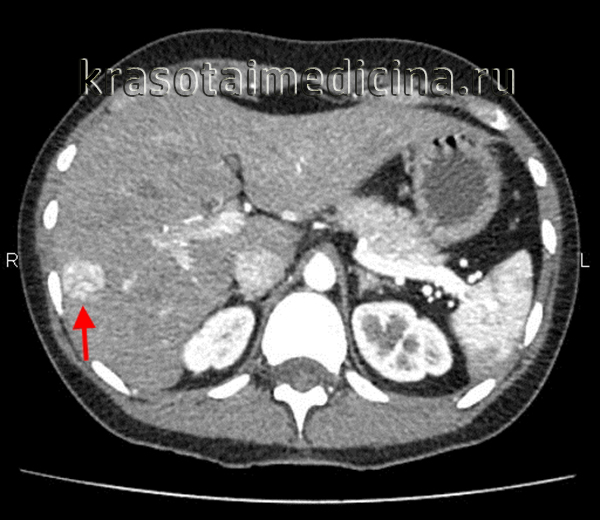

КТ ОБП С+. Гиперваскулярное объемное образование в правой доле печени, соответствующее плотности пула крови во всех фазах – гемангиома